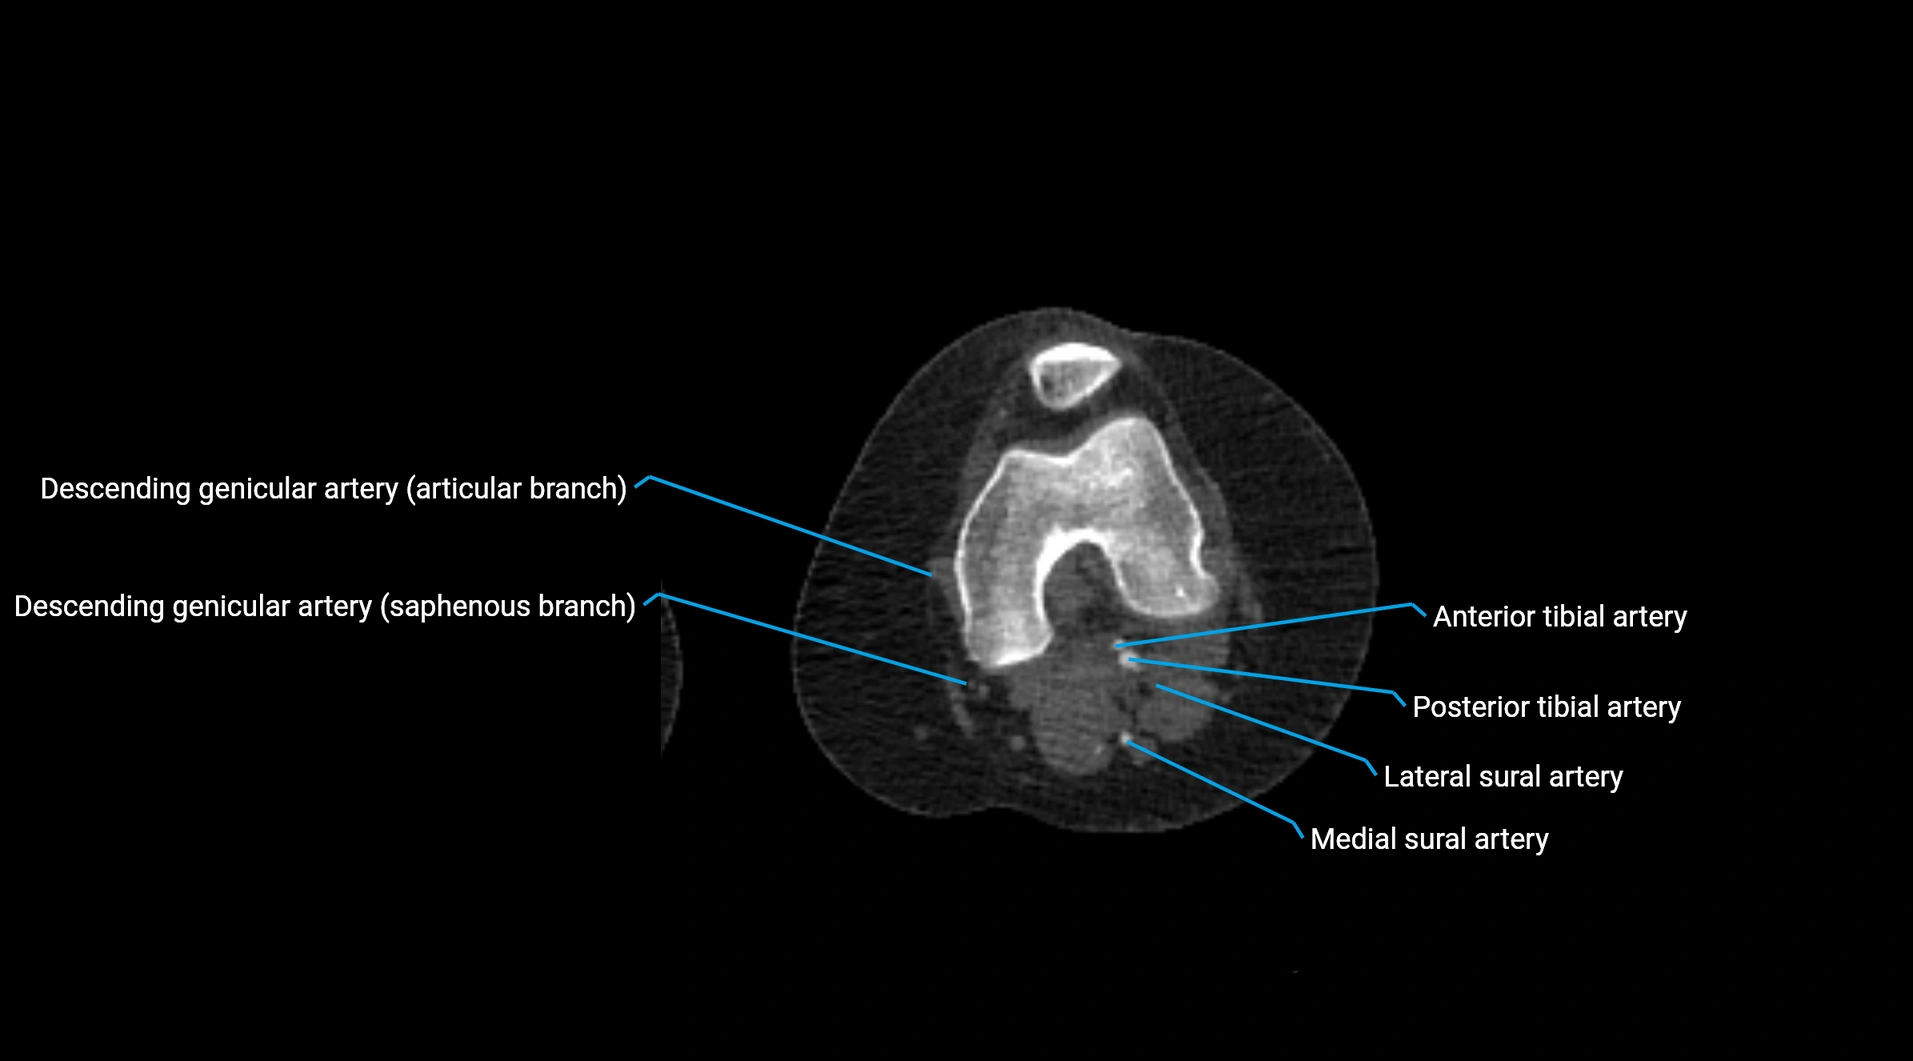

CT Appearance

Non-contrast CT:

• Appears as a tubular soft tissue structure anterior to vertebral bodies

• Calcified atherosclerotic plaques appear as hyperdense foci along the wall

• Useful for screening abdominal aortic aneurysm (AAA) size and mural calcification

Contrast-enhanced CT (CTA):

• Gold standard for abdominal aortic imaging

• Provides excellent detail of lumen, wall, aneurysm, thrombus, and branch vessels

• Multiplanar and 3D reconstructions help in aneurysm measurement, stent graft planning, and dissection evaluation

• Detects acute rupture, traumatic injury, or occlusion with high sensitivity